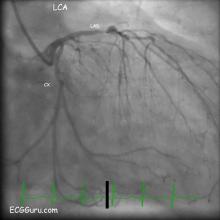

Dominant circumflex artery angiogram

This is an angiogram of a left coronary artery (LCA).  The circumflex artery, labelled CX, is dominant, meaning that it connects to the posterior descending artery and perfuses the posterior and inferior walls of the left ventricle.  Approximately 15-18% of the population has a dominant circumflex artery.  In about 80-85% of people, the right coronary artery (RCA), perfuses the inferior wall.